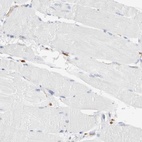

Immunohistochemistry analysis in human bone marrow and skeletal muscle tissues using Anti-ALOX5AP antibody. Corresponding ALOX5AP RNA-seq data are presented for the same tissues.